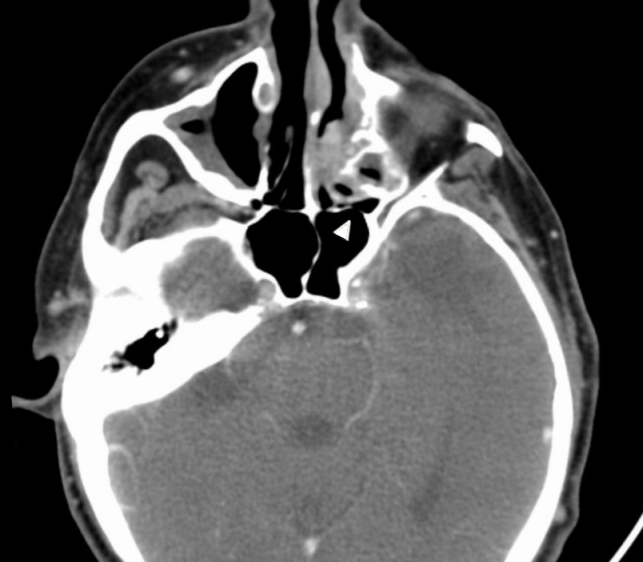

Clinical examination, anterior rhinoscopy and endoscopy revealed purulent secretions and a papilloma-like tumor occupying and obstructing the entire left nasal cavity, and proptosis of the left eye. There was no diplopia, cranial nerve palsy nor palpable cervical lymphadenopathy. Since recurrent IP was suspected, the patient was elected to computed tomogram (CT) of the head and neck area, which showed a heterogeneous opacification of an expansile mass in the left nose and the ethmoid sinus. The medial orbital wall, the anterior wall of the sphenoid sinus and the roof of the left ethmoid sinus were eroded with protrusion of the mass to the left orbit. Nasal septal perforation due to prior endonasal resections was also observed (Figure 1 [Fig. 1] and Figure 2 [Fig. 2]).

Figure 1: Axial CT scan showing destruction of the lateral wall of the maxillary sinus by a heterogeneous tumor in the left nasal cavity. Bone dehiscence of the anterior wall of the sphenoid sinus is also noted (white arrow).